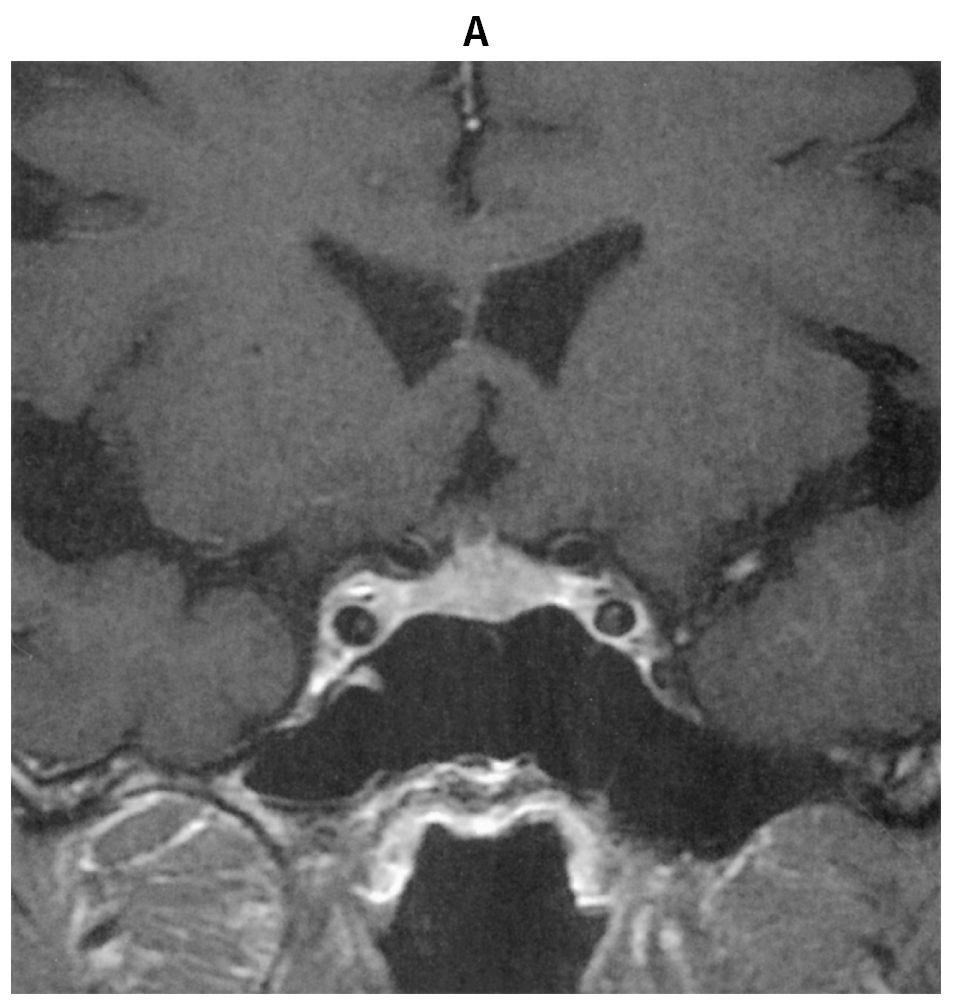

55歳の男性。口渇,多飲および多尿を主訴に来院した。尿量6~8L/日と著明な多尿が数週間続いている。口腔内は乾燥している。尿所見:蛋白(-),糖(-)。頭部造影MRIのT1強調冠状断像(A)と頭部単純MRIのT1強調矢状断像(B)とを下に示す。